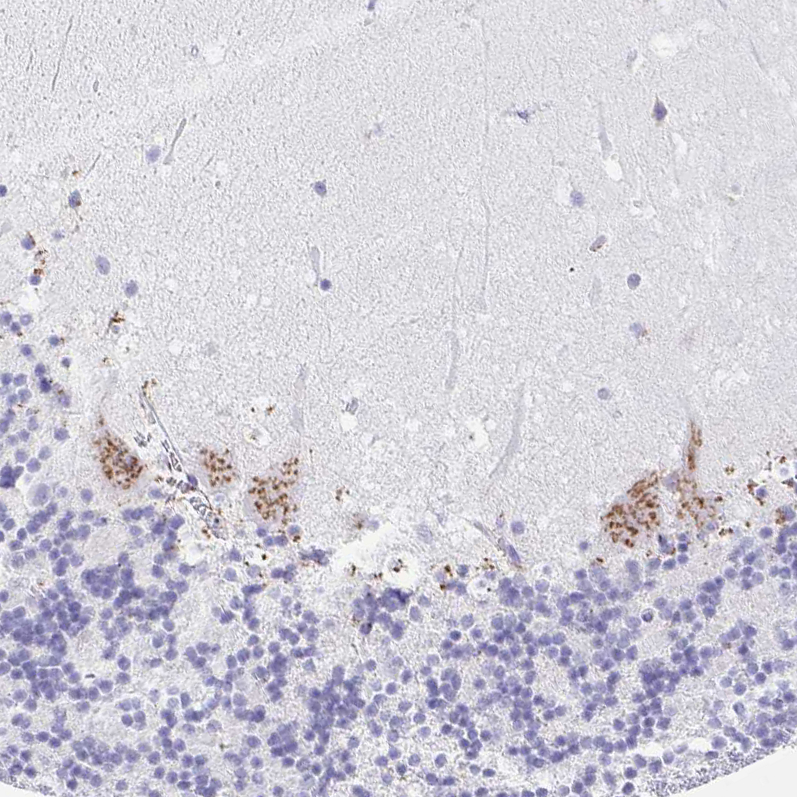

Immunohistochemistry analysis in human small intestine and pancreas tissues using HPA002107 antibody. Corresponding SULT1B1 RNA-seq data are presented for the same tissues.